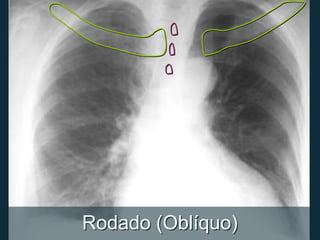

Rodado (Oblíquo)